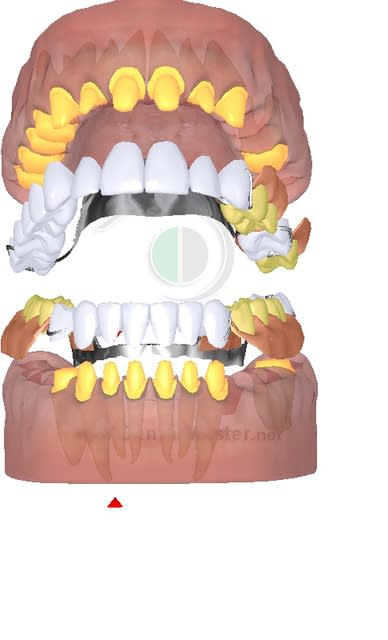

Cas concret comment tu traites ce cas yobi sachant que le mutuelle de la patiente rembourse 200 % sur les IC, 300 % les couronnes en postérieur, et 400 % les couronnes en antérieur ?

1 dokb2v - Eugenol

2 wkewca - Eugenol